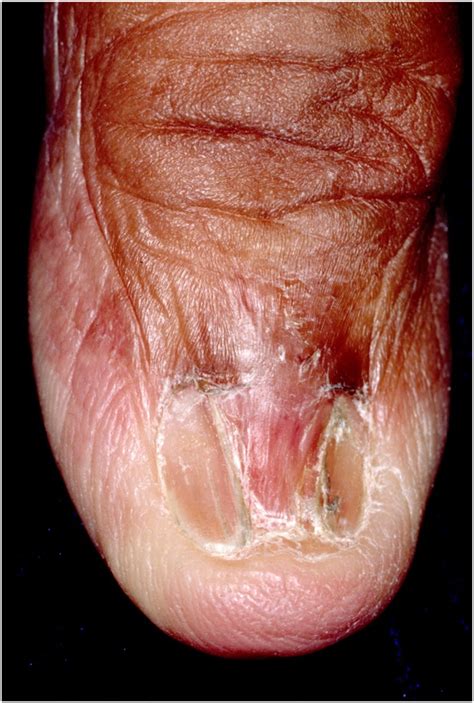

Pterygium on the nail is a condition characterized by the growth of a triangular, wing-like tissue that extends from the cuticle to the nail bed. This tissue can cause the nail to become deformed and may lead to discomfort or pain. The condition is more prevalent in individuals with certain underlying health issues or those who engage in activities that put excessive pressure on the nails.

• Nail Deformity: The most noticeable symptom is the triangular, wing-like tissue that extends from the cuticle to the nail bed, causing the nail to become deformed.